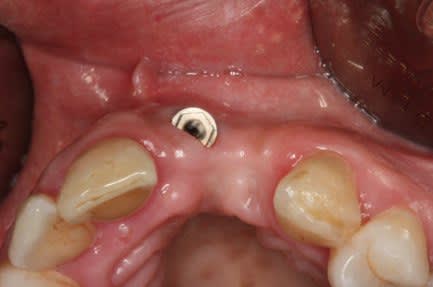

Mais un patient est arrive au cabinet avec 7 Implants maxillaires et rien de plus, bilan des courses , 2 mobiles, 2 avec l'hexagone externe cassé, 1 avec la vis prothétique cassée dans l'implant. Il reste un en place de 17 a moitie enterré et l'autre en 16, ni l'un i l'autre ont une vis de couverture ou un piler de cicatrisation.

P.S : Pour le fun le cas pour lequel , je suis énervé et celui du proces est pire mais je ne peux pas le publier.

Il a laissé la patiente 5 mois comme ça en disant que tout allait bien, l'endo je l'ai faite moi au cas ou !!

Le second va être virer aussi car il est intra-sinusien générant une sinusite chronique.